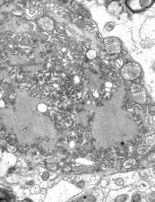

Cysticercosis is a tapeworm larvae infection, while taeniasis is infection with adult tapeworms.[78] Both are found in Asia, Africa, and Latin America, particularly on farms in which pigs are exposed to human excrement.[79]

Cysticercosis is the most common preventable cause of epilepsy in the developing world.[79] Cysticercosis occurs after ingestion of contaminated food, water, or soil.[78] Cysts and lesions can cause headaches, blindness, seizures, hydrocephalus, meningitis, and dementia.[80] Neurocysticercosis, or the parasitic infection of the nervous system, can be fatal. Taeniasis is not fatal.[79][80] It is usually contracted after eating undercooked contaminated pork. Taeniasis has mild symptoms, including abdominal pain, nausea, diarrhea, or constipation.[citation needed]